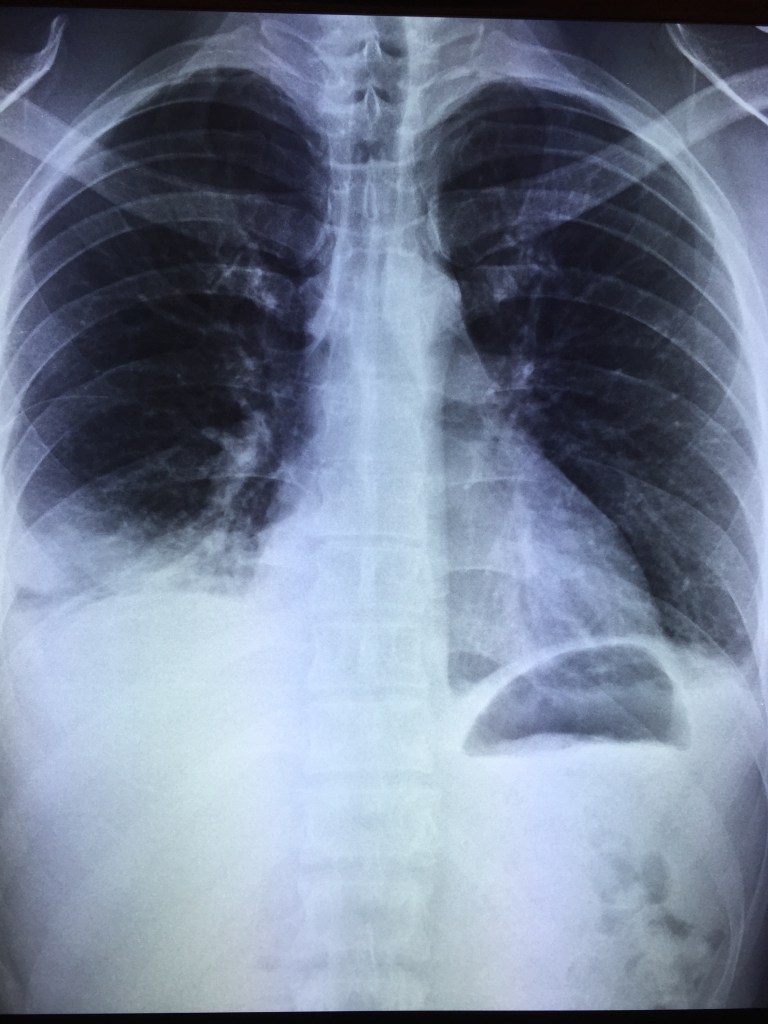

He was prescribed IV ceftriaxone but fever persisted. A day later, his blood cultures flagged positive for MRSA and he was switched to IV daptomycin. A transthoracic 2D-echo showed a normal heart with no evidence of endocarditis. His fever subsided after 2 days of daptomycin and he felt subjectively better. However, on the third day of daptomycin therapy, he experienced right chest wall pain and slight breathlessness on walking to the bathroom. This failed to resolve with symptomatic treatment and chest X-rays were ordered.

One of daptomycin’s unique and less desirable features is that the drug is broken down by lung surfactant, and hence it is inadequate for the treatment of pneumonia. In this particular case, the most likely scenario is a subclinical MRSA pneumonia that worsened even as the patient responded systematically to daptomycin, resulting in clinical pneumonia with parapneumonic effusion (an empyema cannot be completely ruled out at this stage as well, but is unlikely as daptomycin penetrates the pleura in adequate concentrations). He was switched to oral linezolid and recovered without any issues.